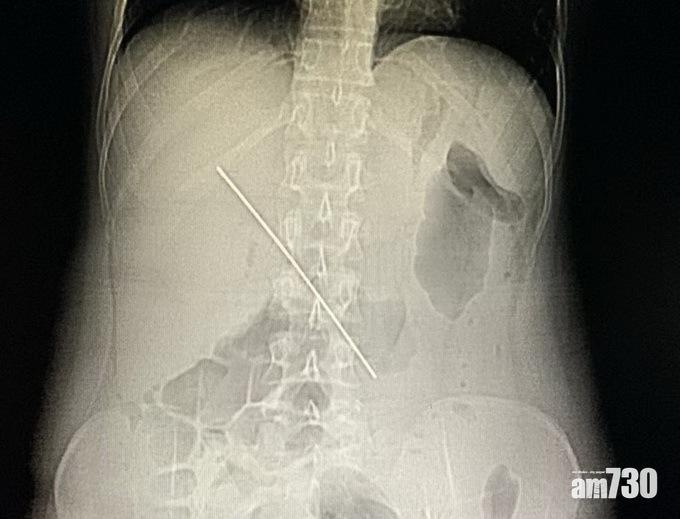

米女體內有一條金屬條。(互聯網)

四川「紅星新聞」報道,當地一名38歲姓米女子連日腹痛難忍,上周五晚到四川大學華西醫院求醫。經CT(電腦掃描)檢查後,醫生赫然發現,米女體內竟有一條頗長的金屬條,幾乎刺進肝臟的大血管「肝門靜脈」,稍有不慎就會造成大出血,甚至一命嗚呼。

醫生最終用內窺鏡為米女取出一條長15厘米、疑似鐵釘的金屬條,米女的腹痛亦隨即減輕。醫生透露,若再過幾小時或半天,「這根長釘很可能刺破肝門靜脈造成大出血」,屆時就要開刀方能取出金屬條。醫生又呼籲,若吞下不明異物,應及時到醫院檢查。

醫生從米女體內取出15厘米長的金屬條。(互聯網)